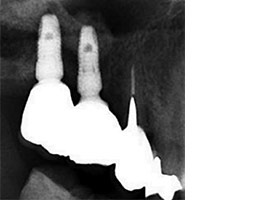

完成時X光片可看見新生骨頭